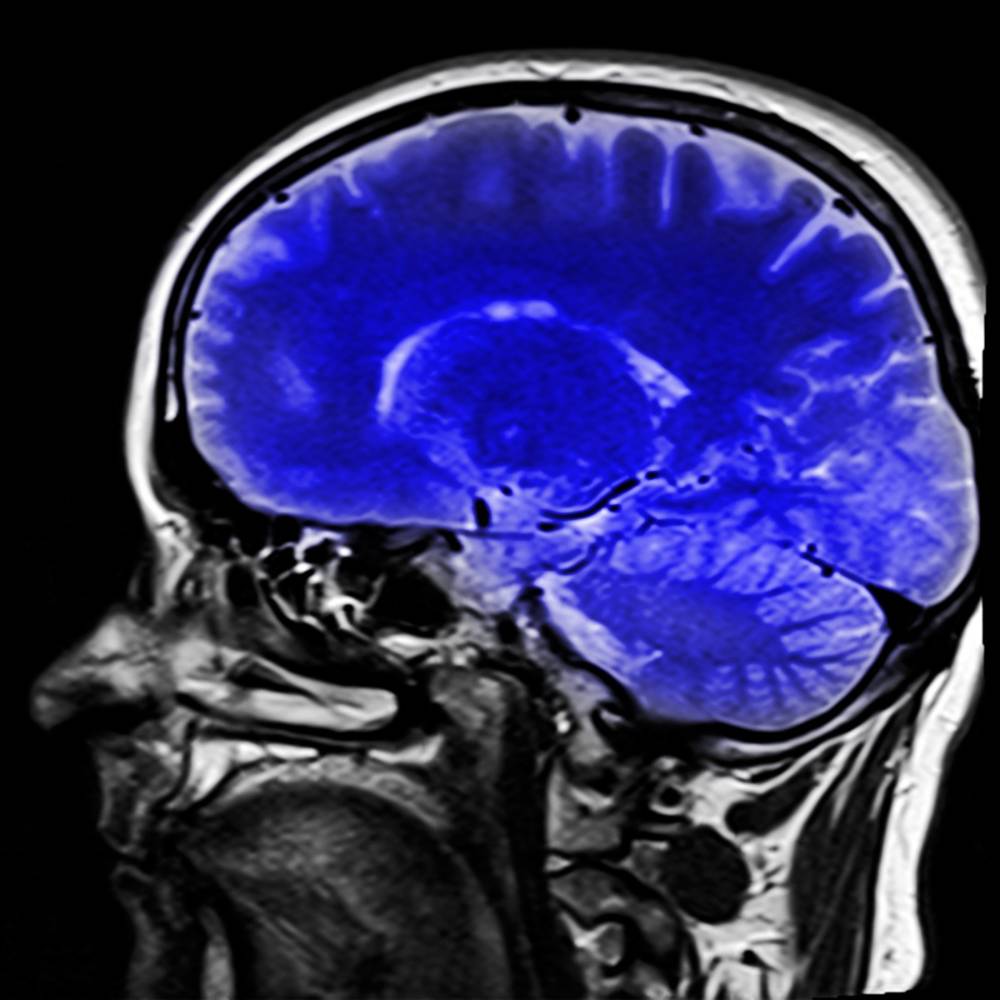

Человеческий головной мозг остается одним из самых загадочных органов, несмотря на доступность процедуры МРТ в Москве, позволяющей получить изображения мозга. Внешний вид этого органа, содержащего 120 миллиардов нейронов, не раскрывает его функционирование и внутренние механизмы. Несмотря на отсутствие конкретных ответов, существует множество интересных фактов о головном мозге, о которых стоит узнать подробнее. Ученые всего мира много лет изучают наш «центральный вычислительный центр» и корпят над своими научными трудами. Но даже несмотря на то, что сейчас запросто можно сделать МРТ головного мозга и просто-таки виртуально препарировать его в 3D, никто пока особо не приблизился к разгадке.

Различные ученые и физиологи пытались сравнить головной мозг с различными аналогиями - от мини-АТС до мощного компьютера. Но даже современные технологии, позволяющие проводить МРТ и виртуальное препарирование мозга, не приблизили нас к полному пониманию работы этого органа.